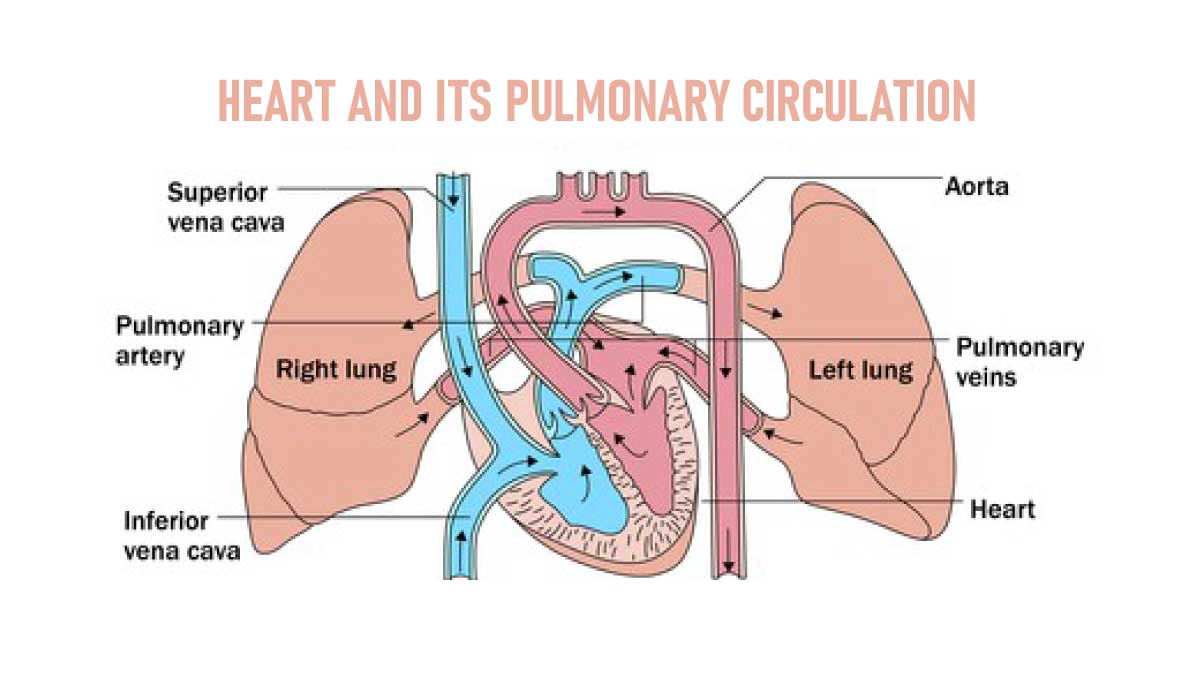

The right ventricle forms the inferior border and a large part of the sternocostal surface of the heart. It is a triangular chamber. The pulmonary trunk and pulmonary arteries take deoxygenated blood from the right atrium and pump it to the lungs.

It is a quadrangular chamber receiving oxygenated blood from the lungs through four pulmonary veins and pumps to the left ventricle through the left atrioventricular or bicuspid or mitral orifice, which is guarded by the mitral valve[bicuspid valve].

The left ventricle gathers and pumps oxygenated blood from the left atrial into the aorta.